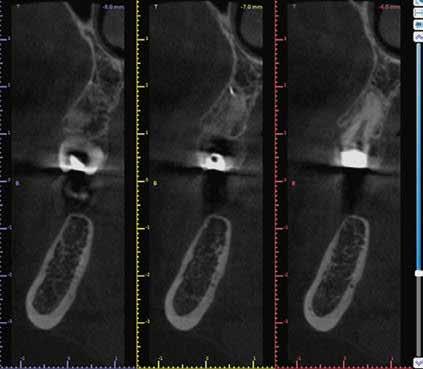

a-m. ábrák: Preoperatív röntgenfelvétel (a) és preoperatív CBCT-felvétel a jobb felső 5-ös (1.5) fogról, sagittalis (b) és axialis (c) nézetek. Az intraorális szkennelés során kapott STL-fájl (d). A 1.5-ös fog navigált endodonciai mikrosebészeti beavatkozásához tervezett sablon (e). A 1.5-ös fog navigált endodonciai mikrosebészeti beavatkozásához nyomtatott sablon (f). Teljes vastagságú mucoperiostealis lebenyt emeltünk (g). A sablont a helyére illesztettük, és a csontablak határait jelöltük (h). A fog gyökerén kívül eső, betört eszköz a 1.5-ös fog periapicalis régiójában (i). Az eltávolított betört eszköz (j). A rezekció, retrográd preparáció és a TotalFill BC RRM Fast Set Putty anyaggal elkészített retrográd gyökértömés utáni röntgenfelvétel (k). A lebenyt varratokkal rögzítettük (l). A kétéves kontroll során készített röntgenfelvétel (m).

Egy 38 éves nőbeteg a korábban kezelt jobb felső második kisőrlőfogából (1.5) kiinduló mérsékelt fájdalom miatt jelentkezett rendelésünkön. A kórtörténetében jelen panasza szempontjából releváns információ nem szerepelt. A beteg a klinikai vizsgálat során vertikális kopogtatásra enyhe érzékenységet jelzett. A kérdéses fog körül mérhető szondázási mélység és a fogmobilitás fiziológiás volt. Periapicalis röntgenfelvételen egy, a fog gyökércsúcsán túl presszálódott betört gyökérkezelő műszerből származó eszközfragmentumot láttunk (2. a. ábra). A preoperatív CBCT-felvétel a buccalis csontlemez épségét igazolta (2. b-c. ábra). A fog revíziója öt hónappal korábban történt. A már előzőleg gyökérkezelt, gyökértömött, majd revideált 1.5-ös fog esetében a diagnózisunk periodontitis periapicalis symptomatica volt. A periapikális elváltozás kezelése érdekében navigált endodonciai mikrosebészeti beavatkozást végeztünk.

A felső állcsontról intraorális szkent (TRIOS) készítettünk, és az ezáltal kapott STL fájlt (2. d. ábra) a CBCT-felvétel során nyert DICOM fájlokkal a Zirkonzahn.Implant-Planner (Zirkonzahn) szoftverben egyesítettük. A sebészi sablont ebben a programban megterveztük, majd a Meshmixer (Autodesk) szoftver se-

gítségével tovább módosítottuk. Az így kapott sebészi sablon egyértelműen meghatározta a periapikális terület eléréséhez szükséges csontablak határait (2. e-f. ábra) Helyi érzéstelenítést követően teljes vastagságú mucoperiostealis lebenyt képeztünk, majd a buccalis csont feltárását követően (2. g. ábra) a sablon segítségével bejelöltük a preparálandó csontablak határait (2. h. ábra). A csontablak kialakítása során Piezotome CUBE LED kézi-darabot alkalmaztunk, majd a leemelését követően a betört eszközt megkerestük (2. i. ábra) és eltávolítottuk (2. j. ábra). A rezekciót ultrahangos megmunkáló fejekkel (ACTEON) végeztük, majd retrográd preparáció következett.

A retrográd gyökértömés elkészítése során TotalFill BC RRM Fast Set Putty-t (FKG) használtunk (2. k. ábra). A lebeny széleit 5/0-s Prolene varratokkal egyesítettük (2. l. ábra). A varratok a műtétet követően 72 órával kerültek eltávolításra. A beteg két évvel később kontrollröntgen készítése céljából érkezett rendelőnkbe. A vizsgálat során a fog tünetmentesnek és funkcióképesnek bizonyult (2. m. ábra).